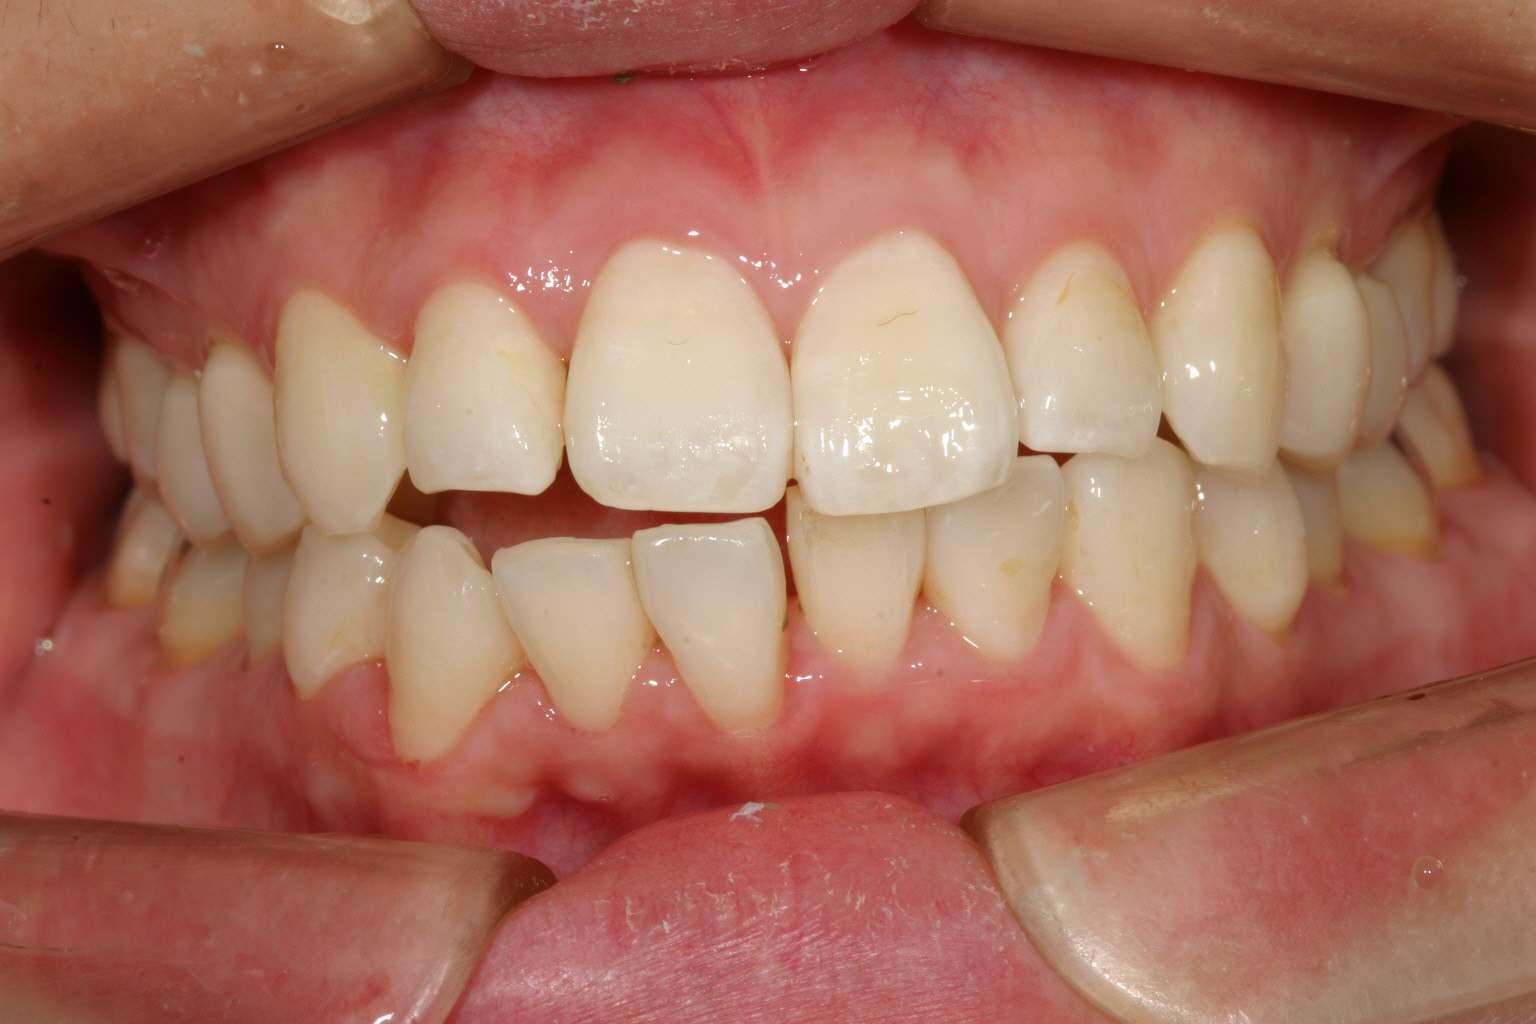

その後半年でここまで改善です。 前から見るとこんな感じです。 ここから再度インビザラインで最終調整です。

綺麗に改善しました。

下顎のガタガタも綺麗に改善しました。

オーバージェットも綺麗になっています。